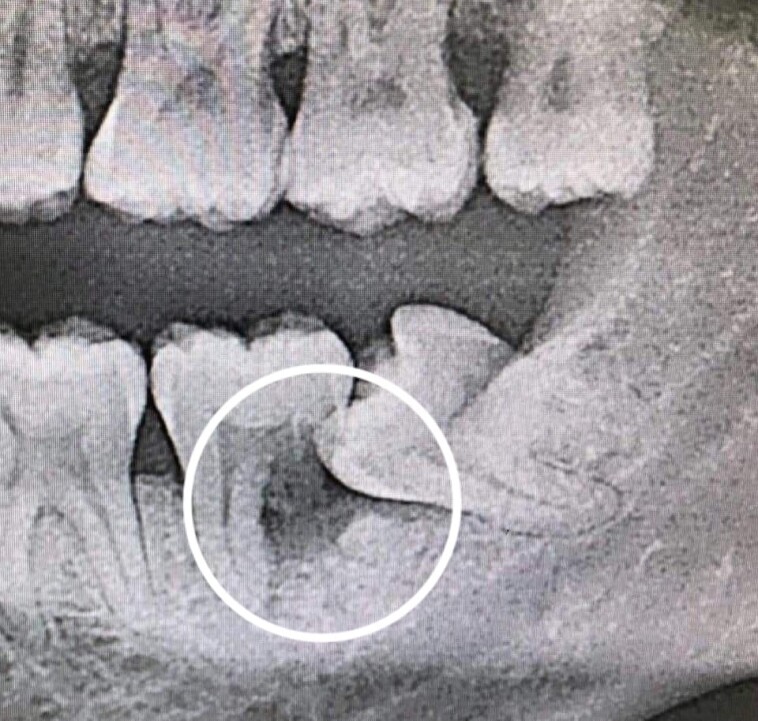

الجواب يعتمد على تقييم الأشعة السينية ووضعية كل ضرس. في كثير من الحالات، يُنصح بخلع الضروس المطمورة أو المنحرفة قبل ظهور الأعراض لتجنب المضاعفات المستقبلية. ومع ذلك، إذا كان الضرس بزوغه سليماً ولا يسبب ازدحاماً أو التهاباً، فقد يوصي الطبيب بمراقبته فقط.